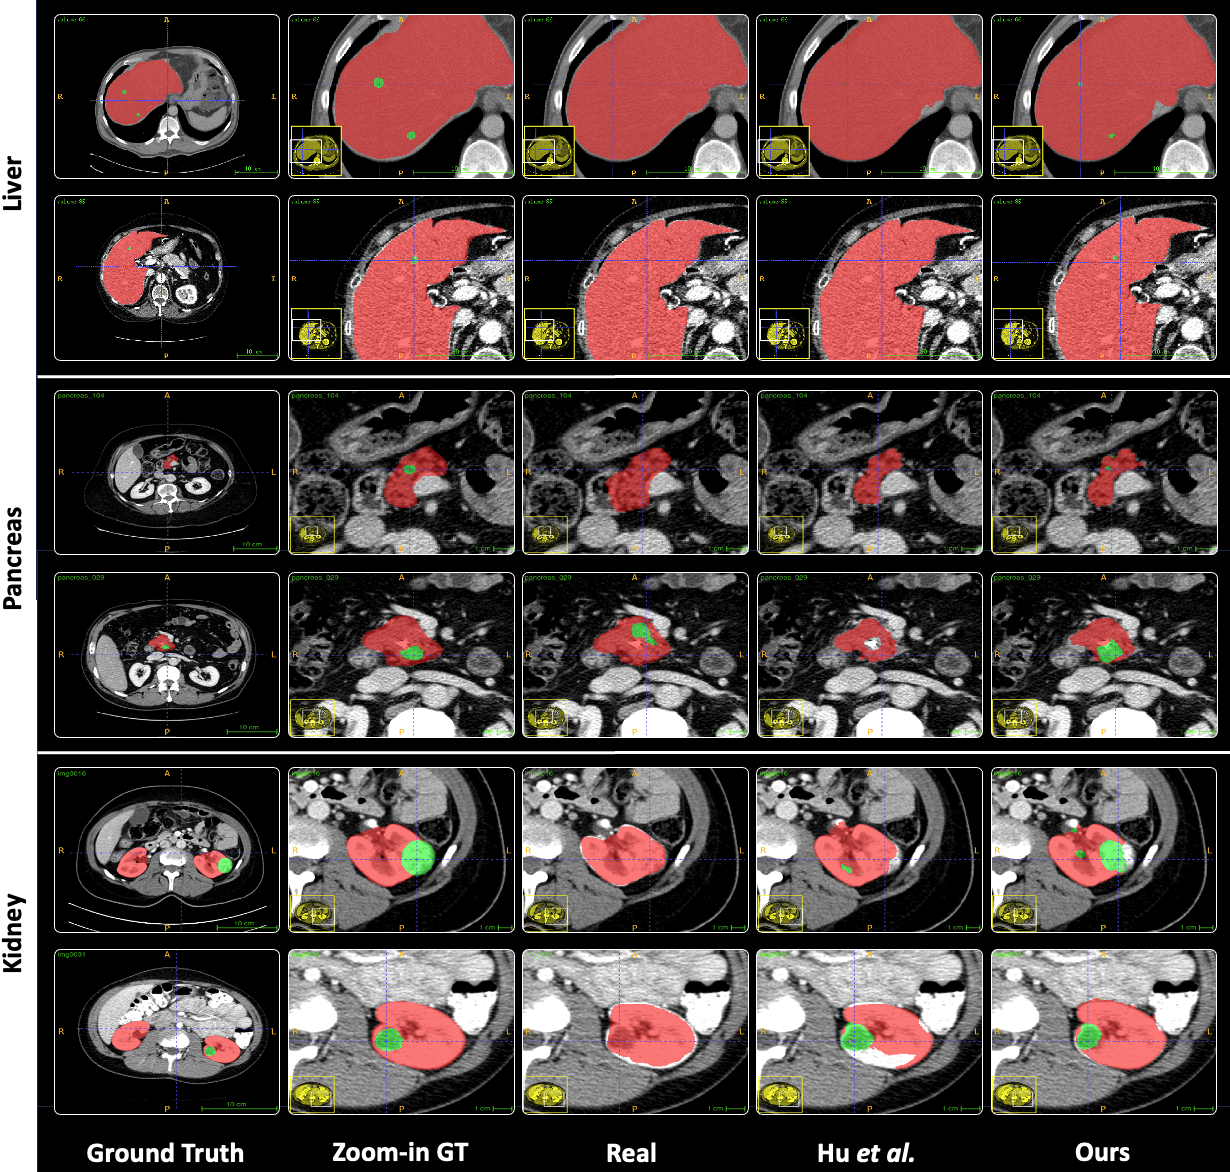

Tumor Segmentation Performance: We benchmark Pixel2Cancer against the state-of-the-art modeling-based method [hu2023label] and real-tumor method [liu2023clip]. Table 2 demonstrates Pixel2Cancer’s superiority in liver segmentation with DSC of 58.9%percent58.958.9\%, and NSD of 63.7%percent63.763.7\%. We also achieve superior performance with real tumors in the pancreas and kidney, with DSCs of 60.9%percent60.960.9\% and 73.2%percent73.273.2\%, respectively. Compared to models trained on real liver tumors, Pixel2Cancer outperforms by 5.7%percent5.75.7\% in NSD. We also surpass Hu et al. by 4.4%percent4.44.4\% in DSC and 6.1%percent6.16.1\% in NSD.

Superiority in Boundary Segmentation: Pixel2Cancer generates synthetic tumors with absolutely precise tumor masks, while real data annotations often have inaccuracies at boundaries, leading to label noise and boundary segmentation inaccuracy. In Table 2, we apply distance metrics (NSD, SD, and HD). Our Pixel2Cancer synthesis approach surpasses real liver tumors, achieving 6.1%percent6.16.1\% improvement in NSD and reductions of 24.7%percent24.724.7\% in SD and 10.8%percent10.810.8\% in HD. These results highlight the precision of Pixel2Cancer in boundary segmentation, indicating its potential for surgical guidance, particularly in tumor excision procedures.

Ability in Small Tumor Detection: Early detection of small tumors is essential for timely cancer diagnosis, but real datasets often lack sufficient instances due to the lack of CT scans in the early stages. Figure 3(b) and Appendix Figure 4 illustrates the performance of small tumor detection. Training solely on our synthetic tumor outperforms models trained on real tumors [liu2023clip] and Hu et al. [hu2023label], highlighting the potential of synthetic tumors for improving early cancer detection.

Refer to caption

Figure 4: Examples of early tumor detection. Qualitative visualizations of segmentation models for liver, pancreas, and kidney tumor detection.